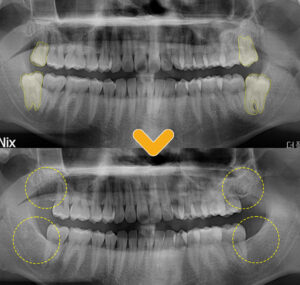

환자분의 상태에서 양쪽 위

사랑니의 경우 올바른 방향으로

머리 부분이 노출된 상태였기 때문에

단순 발치를 진행하여 간단히 발치가 가능합니다.

하지만 양쪽 아래 사랑니의 경우

잇몸뼈 안에 묻혀있는 매복 사랑니의 형태이며,

특히 왼쪽 아래의 사랑니의 뿌리를 보시면

휘어있는 모습이 관찰됩니다.

환자분과의 충분한 상담을 나누었고,

양쪽 위의 사랑니는 단순발치가 가능하지만

아래의 사랑니의 경우

올바른 방향이지만 매복의 형태이며,

뿌리도 휘어있어

난이도가 높은 부분 설명드렸습니다.

따라서 2번에 나누어 오른쪽과

왼쪽 위아래 발치 치료를 하기로 하였습니다.

발치 후의 엑스레이 상에서

꽤 난이도가 있는 발치였음에도 불구하고

남아있는 잔여 조직 없이

깔끔하게 발치된 모습을 보실 수 있습니다.